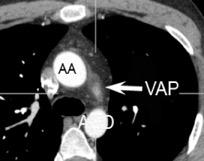

Hodgkin clásico de esclerosis nodular.

Adenopatías región cervical y mamaria interna, prevasculares y VAP. Doble contorno aórtico.